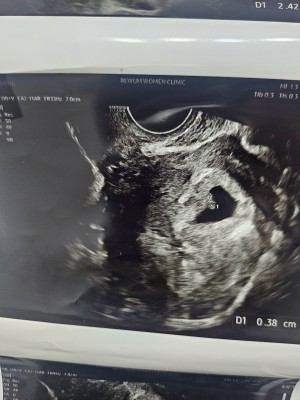

아기집이 두개인건가요?

닉네임_조*민_4

2025-03-24

20

0

초음파사진

닉네임_류*영_3

2025-03-19

8

1